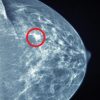

This activity is designed to provide a practical yet comprehensive review into women’s imaging. A multimodality approach to the assessment of pelvic, gynecologic, obstetric and breast disorders is covered in this series. Topics include pelvic pain, pelvic masses, first trimester, uncertain viability, and breast imaging. The renowned faculty share tips and pitfalls regarding the latest protocols and emerging technologies being used to best assess women’s disorders.